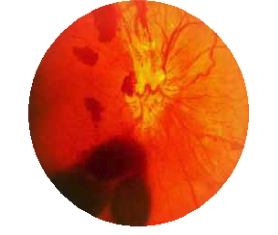

🔍 유리체 출혈(Vitreous Hemorrhage)이란?

눈 속에는 **유리체(vitreous body)**라는 젤리 같은 투명 물질이 가득 차 있습니다.

이 유리체 안으로 혈액이 섞여 들어가 퍼지는 상태를 유리체 출혈이라고 합니다.

- 정상적으로는 혈관이 없고, 완전히 투명해서 빛이 망막에 도달할 수 있게 해줌

그런데 유리체에 출혈이 생기면, 피가 빛의 통과를 막아 시야가 흐려지거나 가려짐